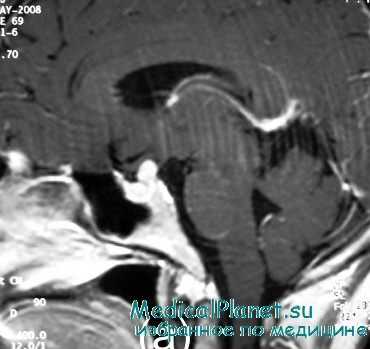

- Нейровизуализация. Чтобы обнаружить органические поражения гипоталамо-гипофизарной зоны, проводится рентгенография турецкого седла, МРТ или КТ головного мозга. При необходимости обследование дополняется церебральной ангиографией, электроэнцефалографией.

- Методы медицинской визуализации. Прицельный рентгенологический снимок турецкого седла позволяет выявить уменьшение размеров железы. Более подробную информацию о структуре и изменениях органа предоставляют томографические методики (МРТ, компьютерная томография).

5. КТ головного мозга.